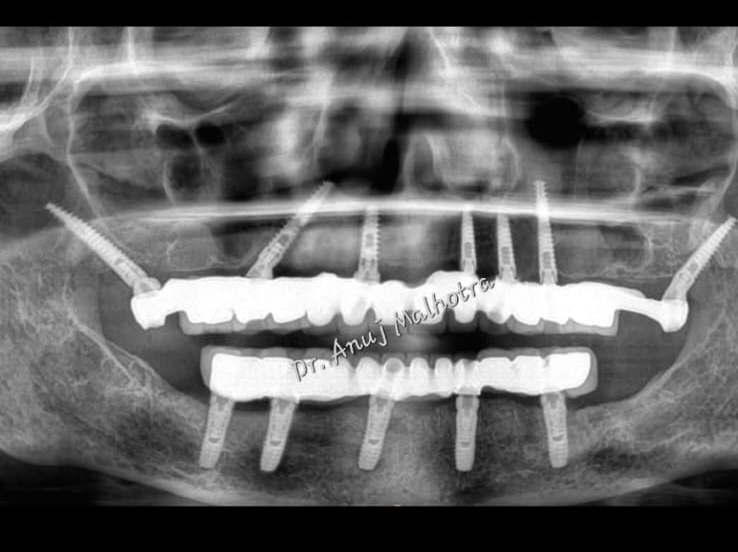

Full Mouth Implant Case